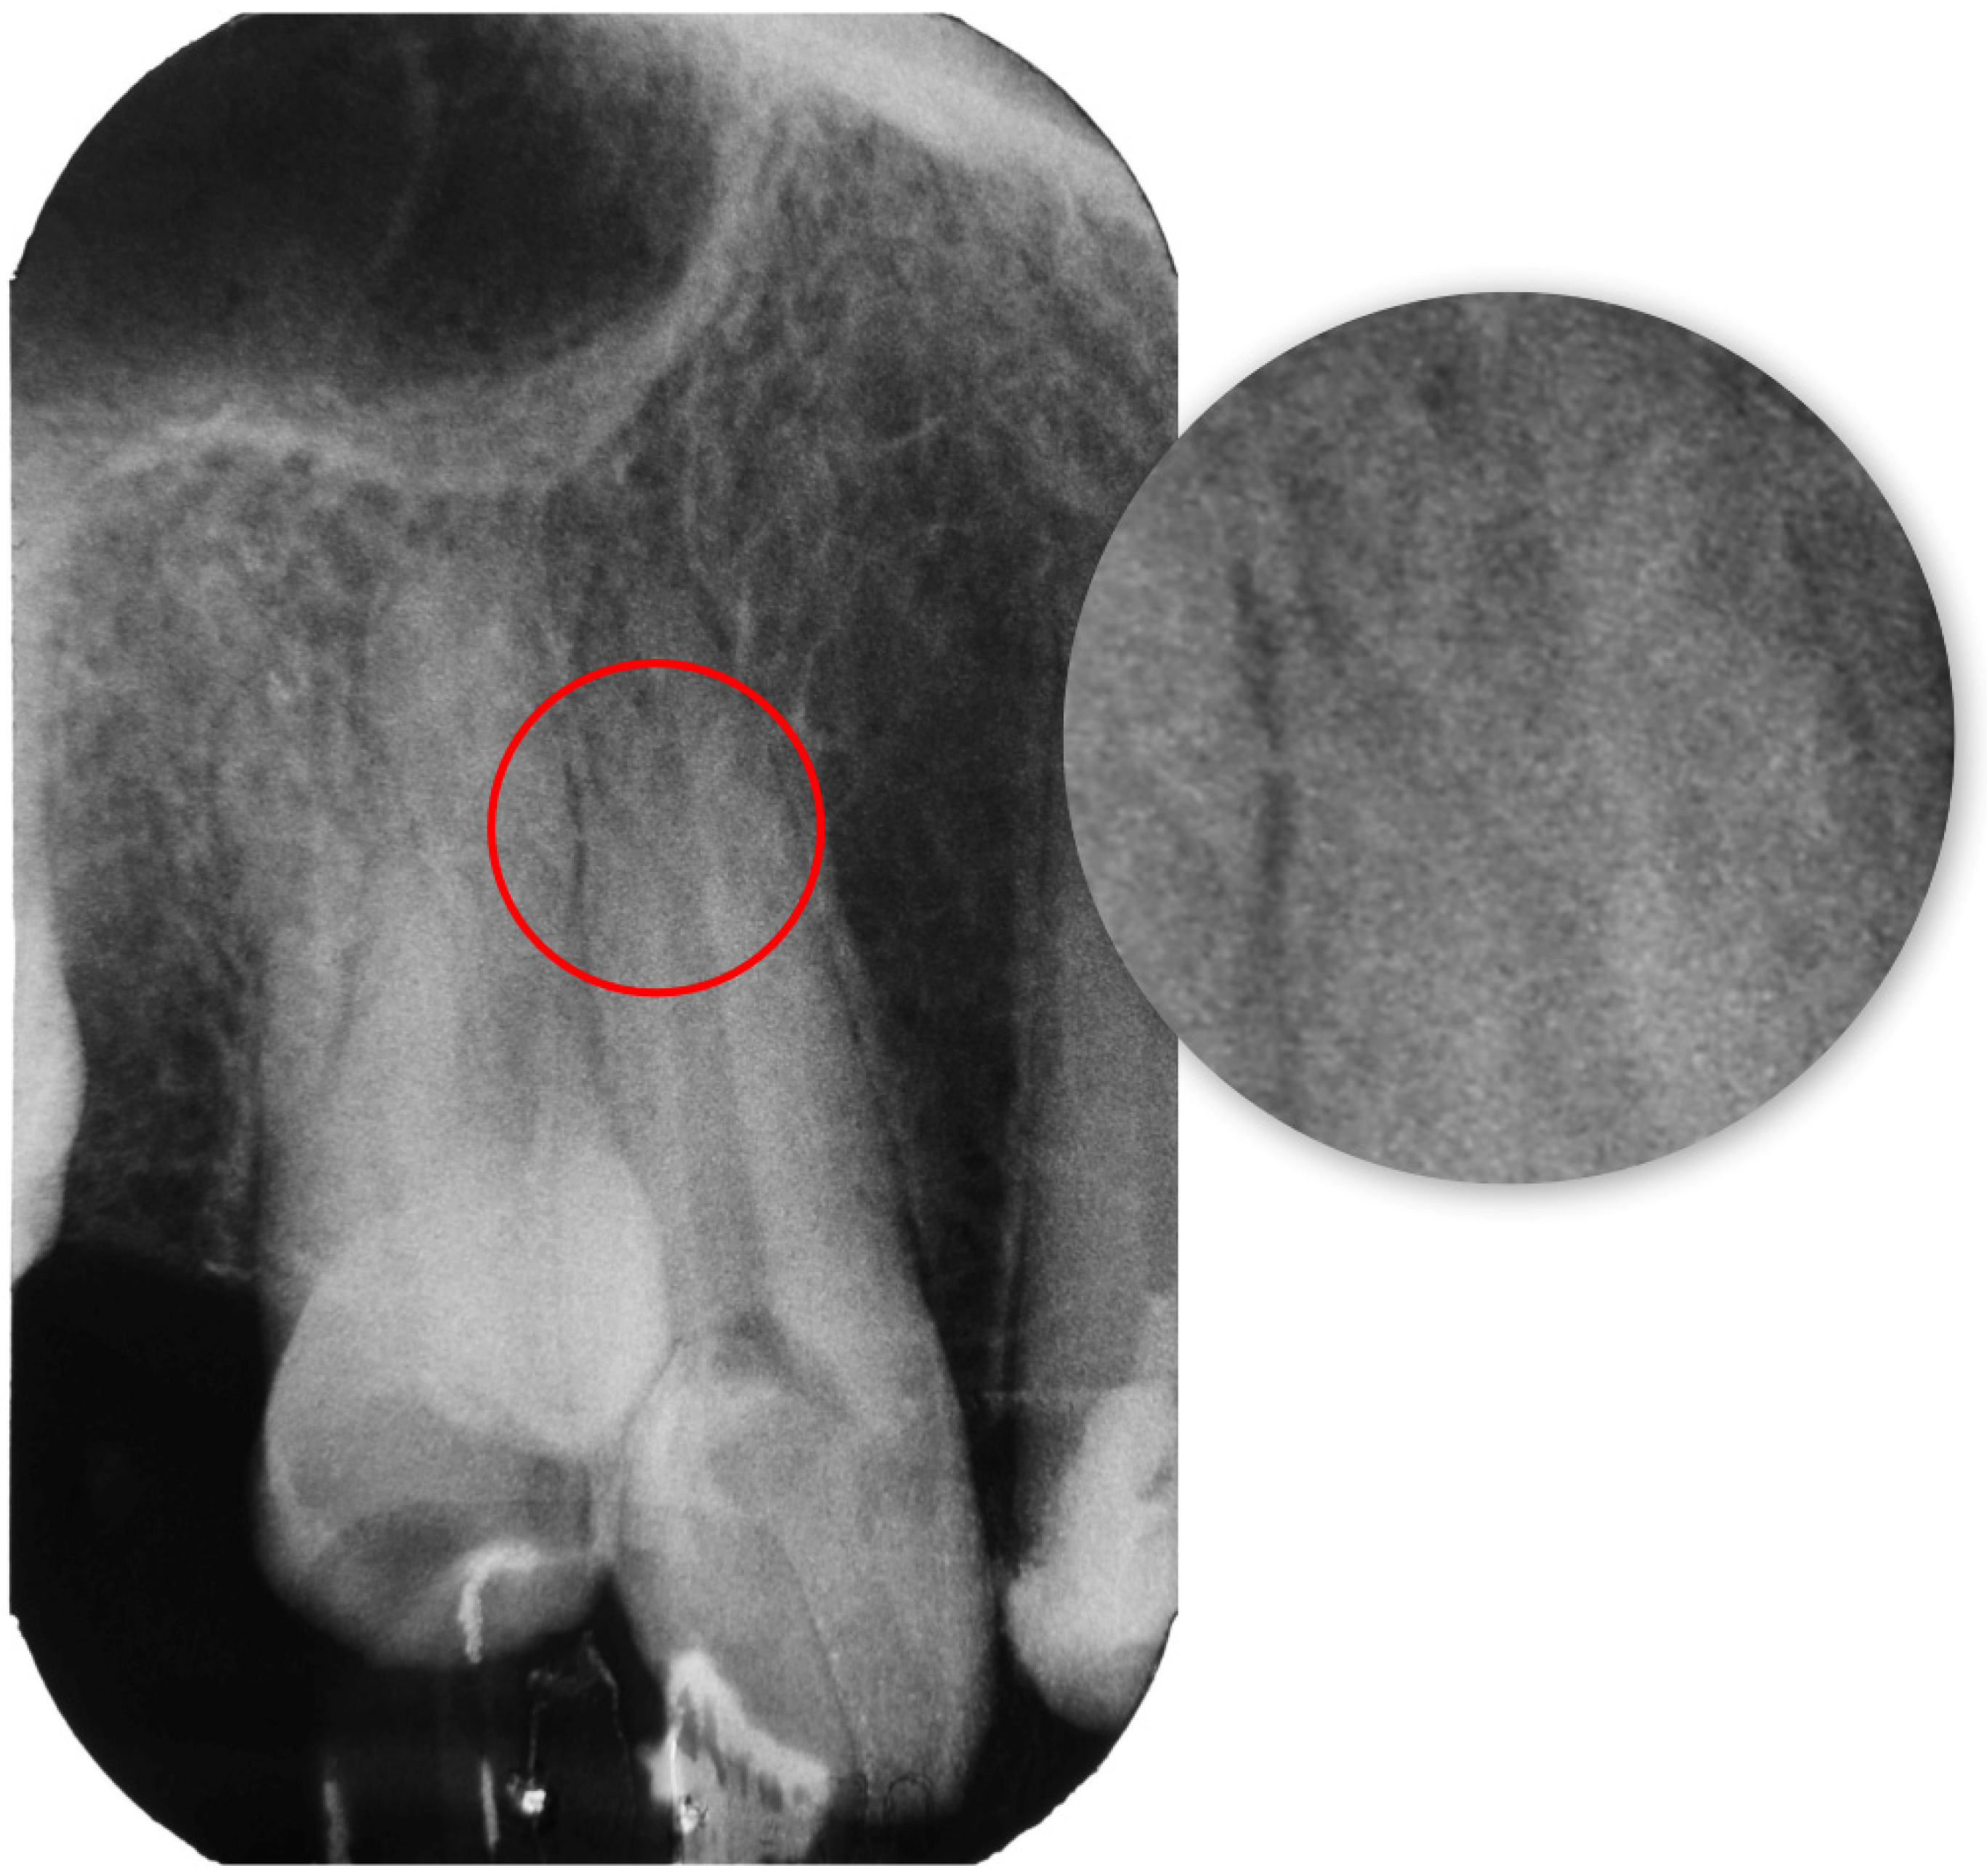

2.1. Report A

2.2. Report B

2.3. Report C

2.4. Report D